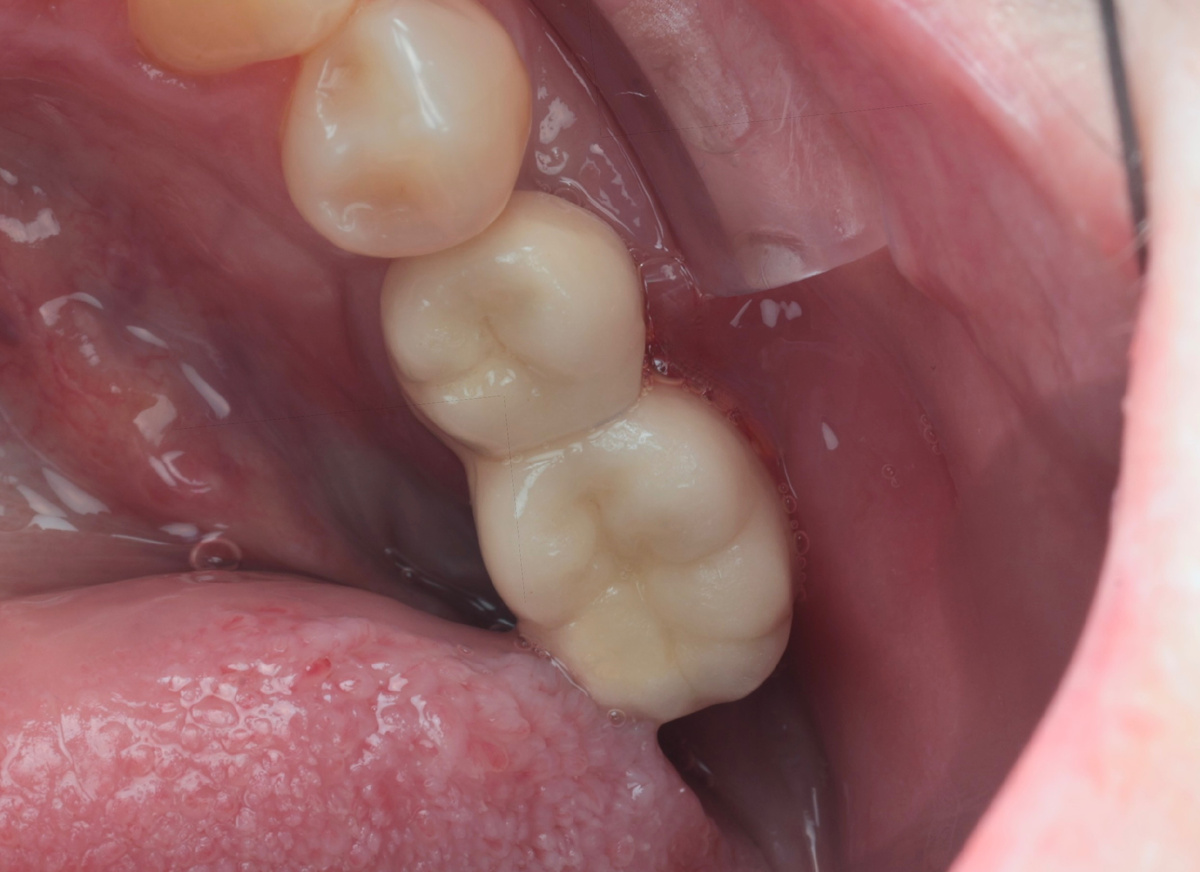

К нам обратилась пациентка с имплантататами, установленными более 10 лет назад. На имплантататах - металлокерамические коронки:

Жалобы - отёчность дёсен, кровоточивость, гноетечение, оголение имплантататов.

Убрали коронки: